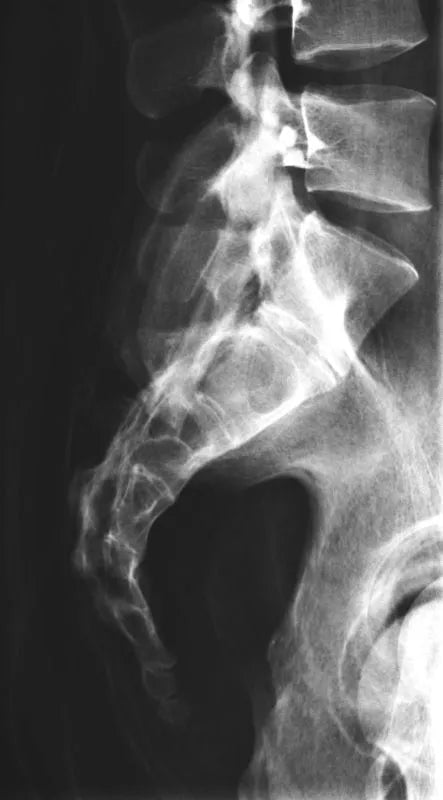

The whole-body X-ray phantom serves for practical training in projection radiography as well as in positioning and positioning techniques. It enables the production of realistic X-ray images under training conditions and depicts anatomical structures in their natural size.

The phantom contains a natural human skeleton. Additionally, the outlines of the larynx, lungs, heart, and kidneys are integrated, appearing as shadows on the X-ray images. This allows for the creation of images that accurately reflect the conditions found in patients. The use of a real skeleton enables the identification of bony landmarks that are not visible in plastic models.

The joints are mounted with full mobility, allowing positioning in common radiological standard positions, including special positions such as the frog position and pronation and supination of the forearm. The arms can be raised, so the phantom can also be used for bone examinations in CT scans. Particular attention was paid during assembly to the realistic representation of the joint spaces.

Each phantom is a handcrafted, unique piece. Variations in size, design, and appearance are possible. Depending on the model, pathological findings may be present. The revised design was developed in collaboration with a German training institution for medical-technical radiology assistants and meets the requirements of modern training concepts.